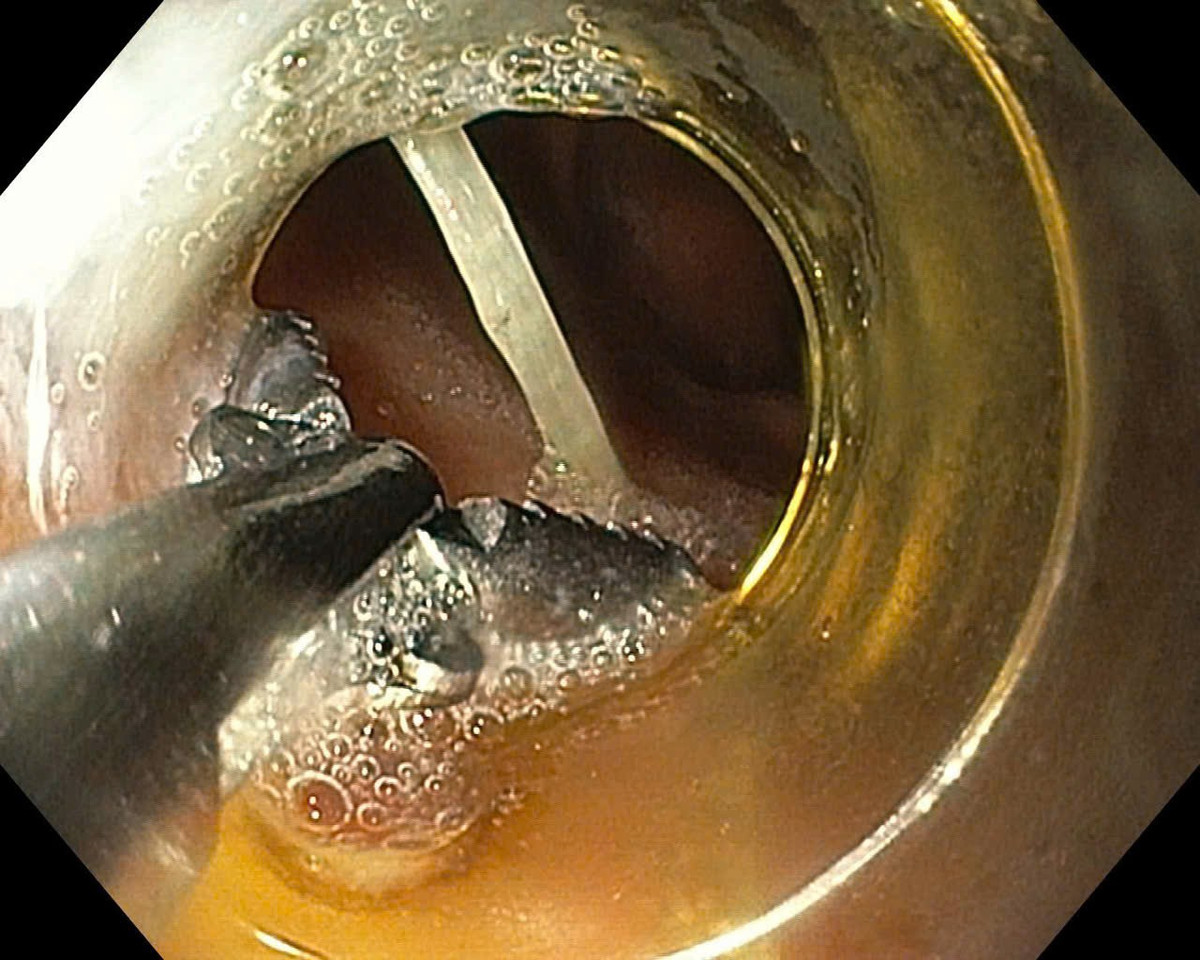

Tại đây, sau khi tiến hành điều tra bệnh sử thăm khám lâm sàng, các bác sĩ đã chỉ định nội soi dạ dày thực quản cho cô L. Qua hình ảnh nội soi, bác sĩ phát hiện có một mảnh xương cá nằm ở dạ dày kích thước khoảng 3 cm, 2 đầu xương cá cắm vào thành dạ dày.

Xương cá đâm trong dạ dày bệnh nhân - Ảnh BVCC

Các bác sĩ đã dùng dụng cụ chuyên dụng lấy dị vật ra ngoài, thấy có ít dịch mủ chảy ra. Sau đó bệnh nhân được cho nhập viện theo dõi thêm, hiện tại tình trạng sức khỏe bệnh nhân đã ổn định.